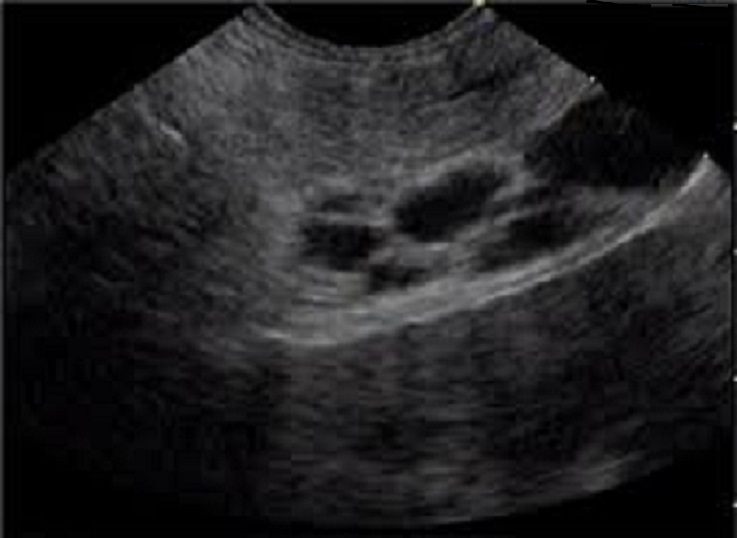

Image echographique d'une TIPMP du pancreas est image

de kyste de aechogen unique ou multiple du parenchyme du pancreas

avec image de dilatation de plus > 5mm hypoechogen du canal

pancreatique principale . Endo echographie parfois image de

communication du kydt avec canal pancreatique dilate

Aspect

echographique de multikystique aechogen d'une tumeur

intracanalaire papillaire mucineux du pancreas avec

image de comunication cannalaire avec canal

pancreatique du pancreas . Le canal pancreas

est peu dilate . |